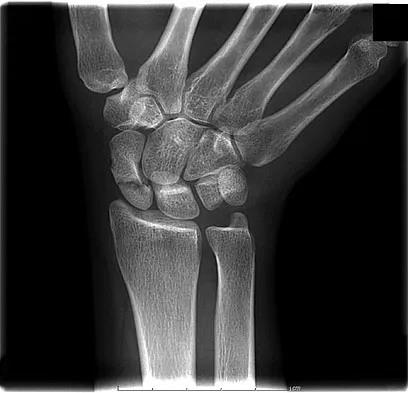

A 19-year-old woman fell onto her nondominant hand 6 weeks ago. Radiographs are shown in Figures 37a and 37b. A decision has been made to treat this fracture surgically. What is the best approach to treat this fracture?

Explanation

Displaced fractures of the scaphoid are best treated with compression screw fixation. Proximal third fractures (as in this patient) are optimally approached via a dorsal approach to ensure proper reduction and compression. Fractures of the scaphoid waist can be approached either by a volar or a dorsal approach. Kirschner wire fixation is limited to proximal pole fractures that are too small to accommodate the trailing head of a compression screw. Retting ME, Raskin KB: Retrograde compression screw fixation of acute proximal pole fractures. J Hand Surg Am 1999;24:1206-1210.